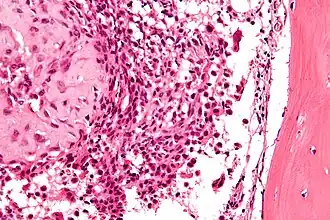

![]() Микрофотография хондробластомы. Окрашено гематоксилином и эозином | |